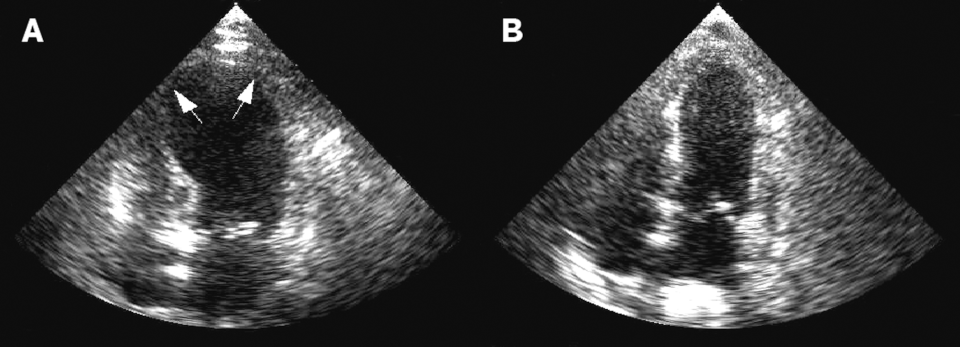

Синдром разбитого сердца: ЭхоКГ в остром периоде и через 6 дней - nicetry.blog

Синдром разбитого сердца: ЭхоКГ в остром периоде и через 6 дней.

Слева — острый эпизод с дилатацией ЛЖ, справа — частичное восстановление через 6 дней.

(Автор(ы): Tara C. Gangadhar и соавт., Journal of Medical Case Reports)